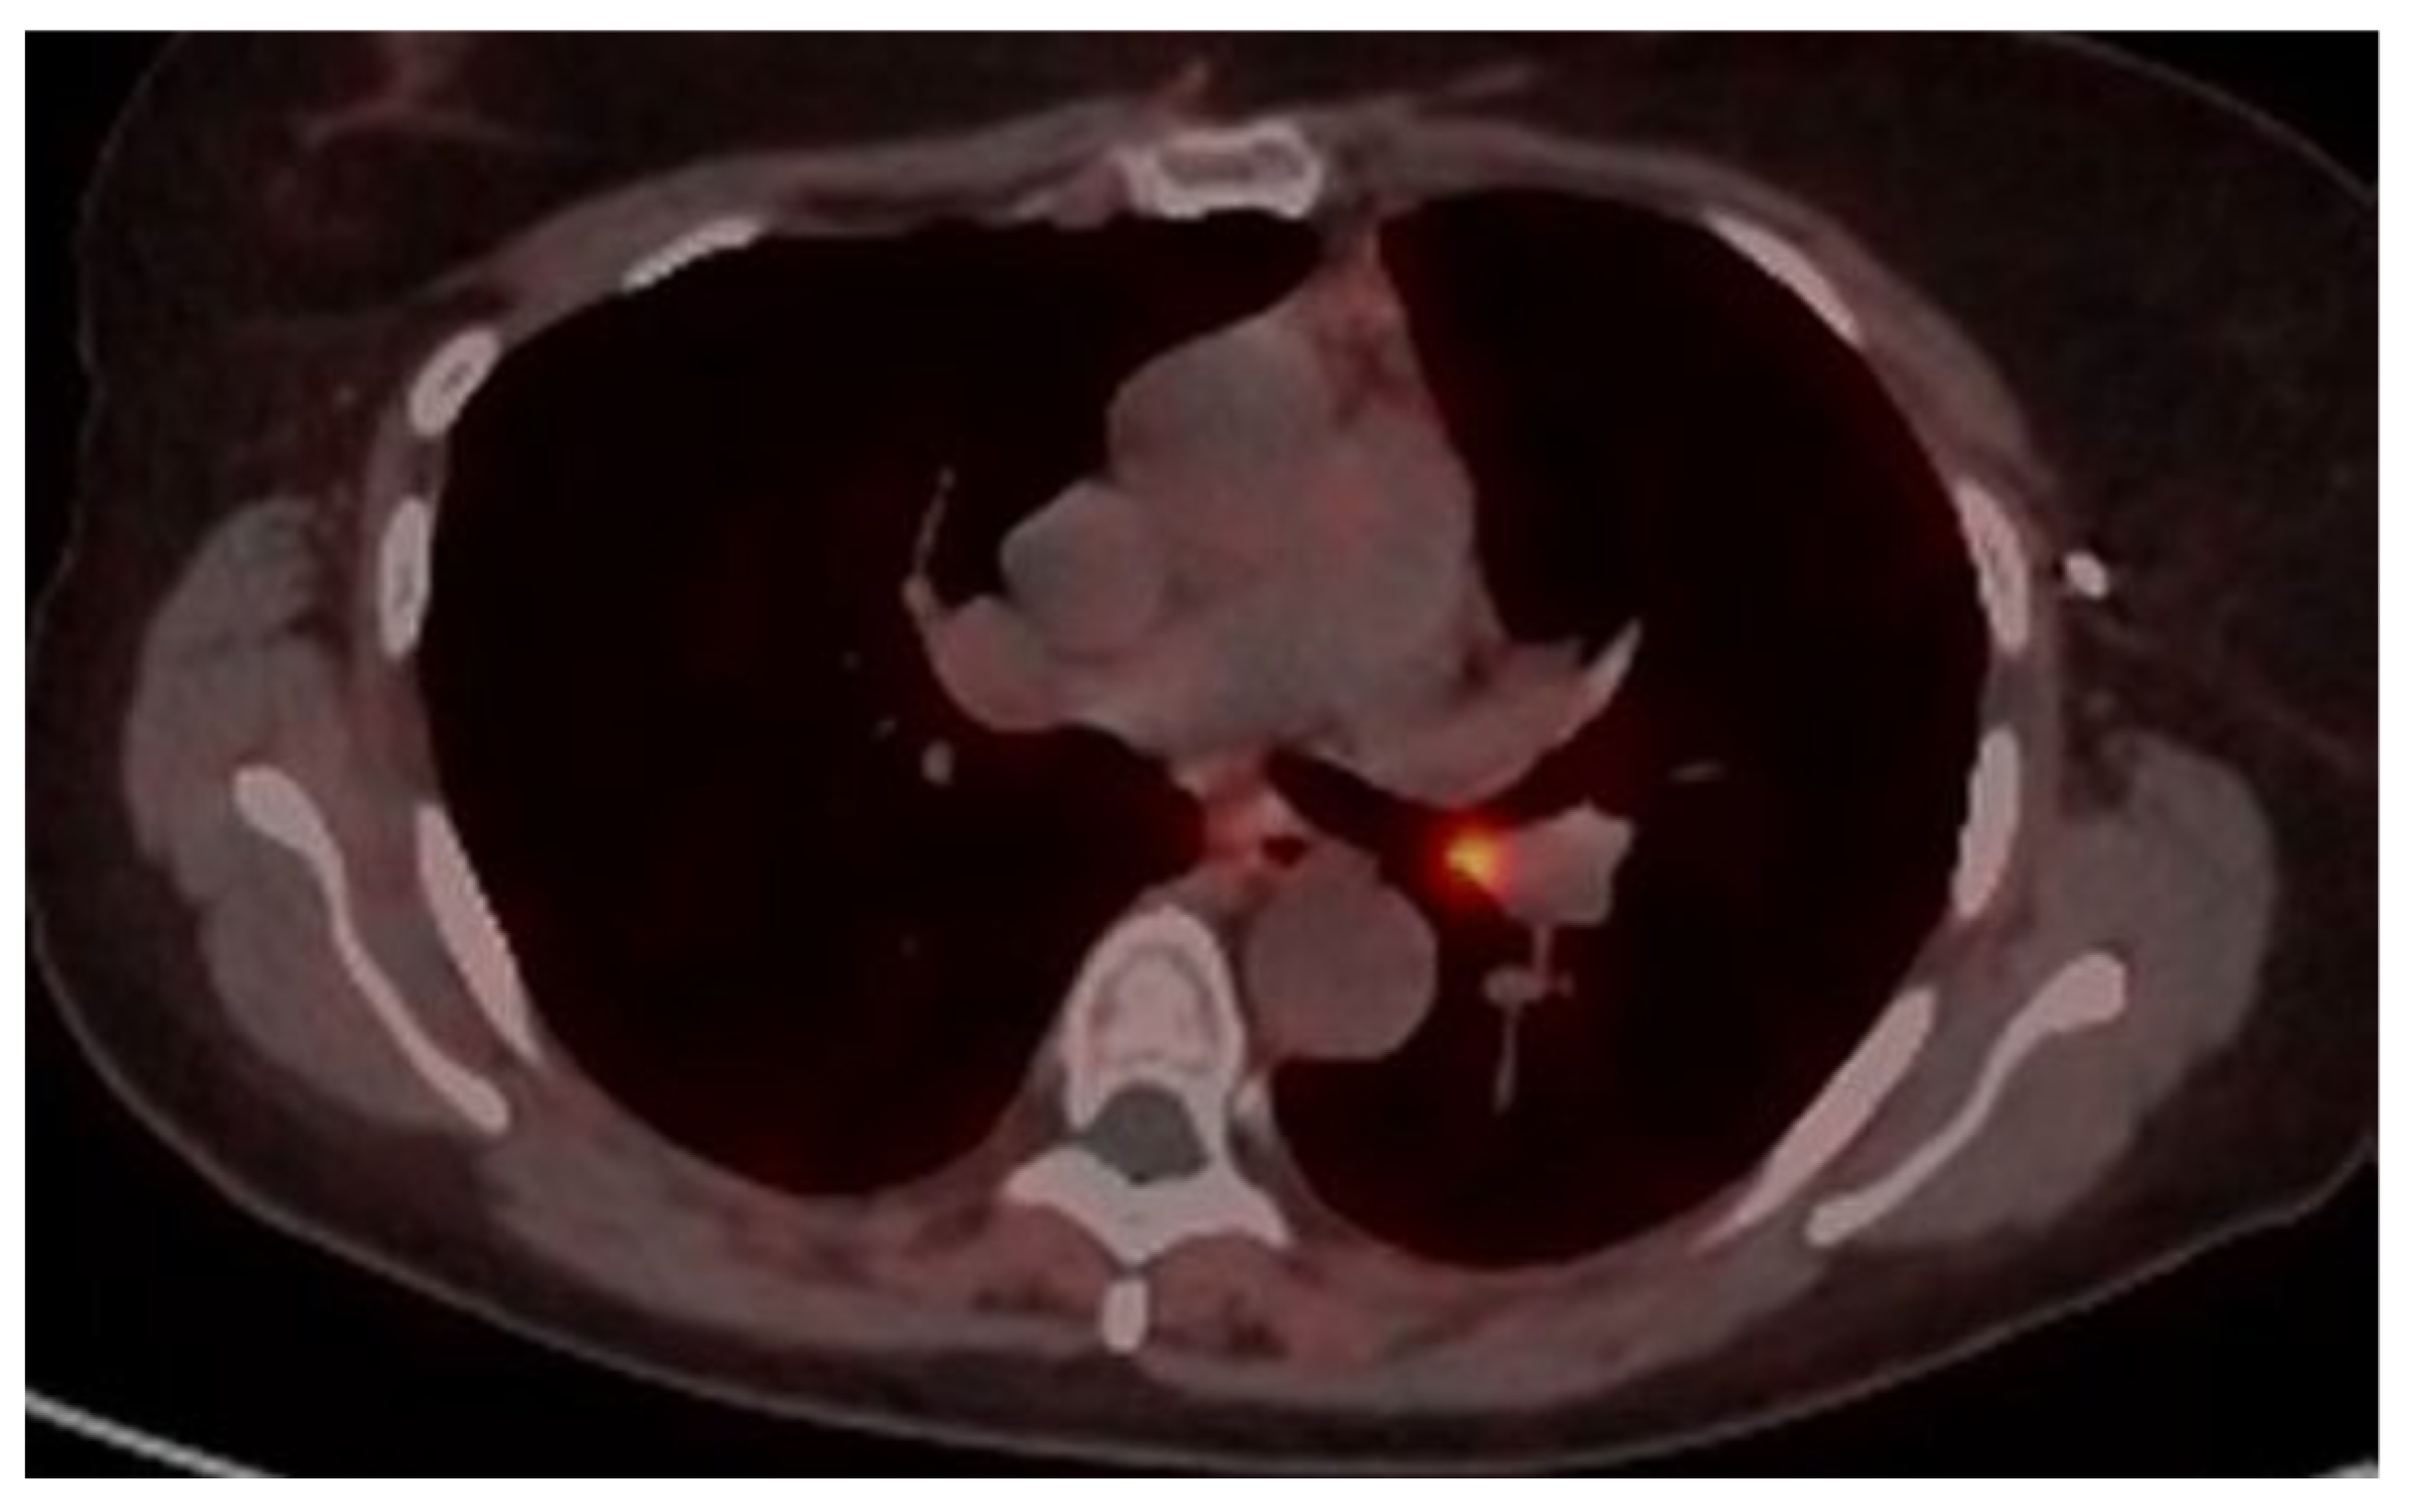

4.1. Case 1